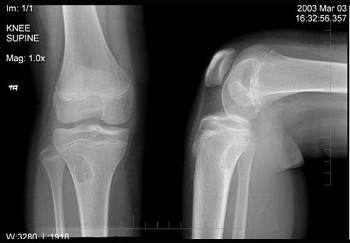

第四,请准备好您自己的摄片,比如X光片CT或者核磁片子,以便带入手术室,术前排尽大小便,也不要把一些随身物品带入手术室。